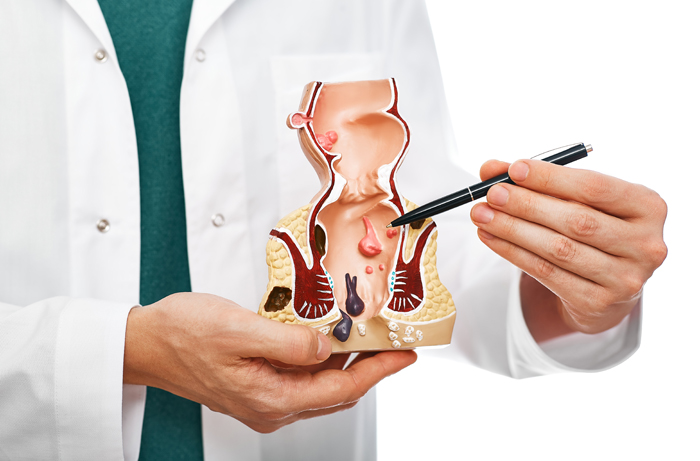

Piles (Hemorrhoids) are swollen veins in the rectum or anus that cause pain, bleeding, itching, and discomfort. With modern treatment methods, piles can be cured safely and quickly, helping patients return to normal life without pain.

A fistula is an abnormal tunnel formed between the anal canal and the skin. It causes pain, swelling, discharge, and recurring infections. Early treatment is important to prevent complications and ensure complete healing.

A fissure is a small tear in the lining of the anus that causes sharp pain, bleeding, and difficulty during bowel movements. Proper treatment helps relieve pain, heal the tear, and prevent it from becoming chronic.

A fistula is an abnormal tunnel that forms between the anal canal and skin, causing swelling, pain, and recurring infections. Dr. Jitendra Kumar Yadav specializes in precise diagnosis and effective treatment of fistula, using modern techniques to ensure minimal discomfort and faster healing. Patients benefit from tailored care plans and thorough guidance throughout the treatment process.

Rectal polyps are abnormal growths in the rectum that can lead to discomfort and health complications if untreated. Dr. Jitendra Kumar Yadav provides accurate diagnosis and modern treatment options to remove polyps safely and efficiently. Patients are guided through every step, ensuring comfort, understanding, and a smooth recovery.

Anal fissures are small tears in the lining of the anus that cause sharp pain and bleeding during bowel movements. With Dr. Jitendra Kumar Yadav’s expertise, fissures are treated effectively using advanced, minimally invasive techniques. Patients receive personalized care, advice on preventive measures, and fast recovery solutions at Apolo Clinic, Mustafabad, District Siwan.

Piles, also known as hemorrhoids, can cause pain, bleeding, and discomfort during daily activities. Dr. Jitendra Kumar Yadav provides safe and advanced treatment options that are minimally invasive, ensuring quick recovery and long-lasting results. At Apolo Clinic, Mustafabad, patients receive personalized care and clear guidance from the initial consultation to full recovery.